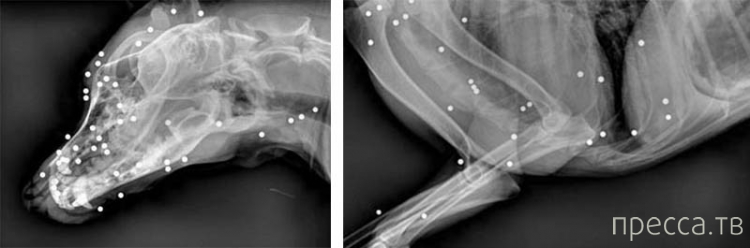

В теле собаки застряло около 100 пуль. В одной только голове животного было 50 пуль (фото: Mail Online)

Рентгеновский снимок животного показал, что в теле у пса застряло около ста пуль. Собаке потребовалась срочная операция, во время которой специалисты извлекли все поражающие элементы.

- Леди явно очень повезло, - поделилась оперировавшая ее врач-ветеринар. - По счастливой случайности ее глаза остались невредимыми. У нее не были задеты жизненно важные органы. Вы только представьте - в голове у собаки было почти 50 пуль!

В теле собаки застряло около 100 пуль. В одной только голове животного было 50 пуль (фото: Mail Online)

Рентгеновский снимок животного показал, что в теле у пса застряло около ста пуль. Собаке потребовалась срочная операция, во время которой специалисты извлекли все поражающие элементы.

- Леди явно очень повезло, - поделилась оперировавшая ее врач-ветеринар. - По счастливой случайности ее глаза остались невредимыми. У нее не были задеты жизненно важные органы. Вы только представьте - в голове у собаки было почти 50 пуль!